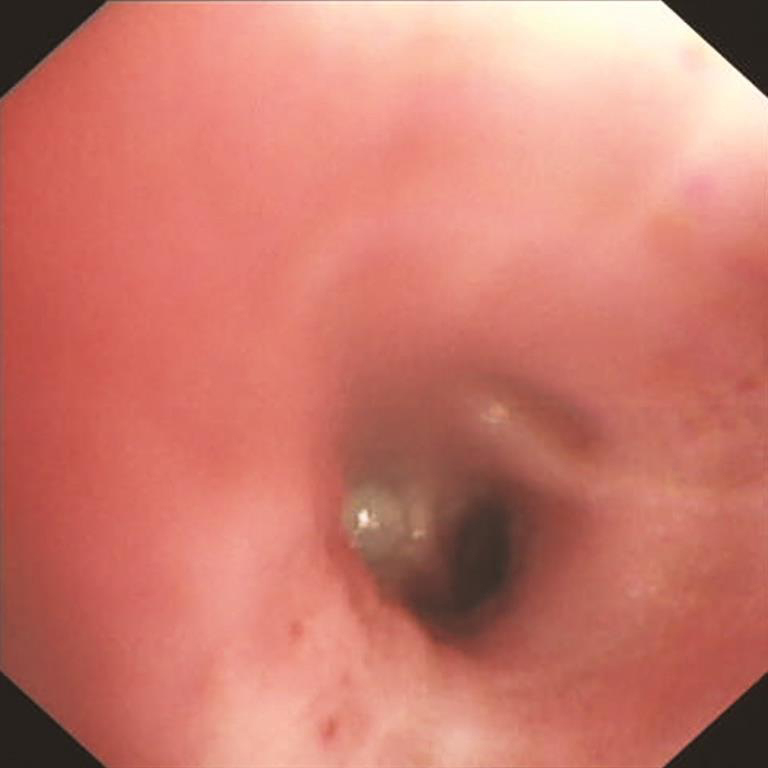

【支气管镜检查】

镜下见右下前基底支一亚支开口狭窄,可见分泌物溢出;径向EBUS探查见占位性病变(图3)。

图3 支气管镜检查镜下所见